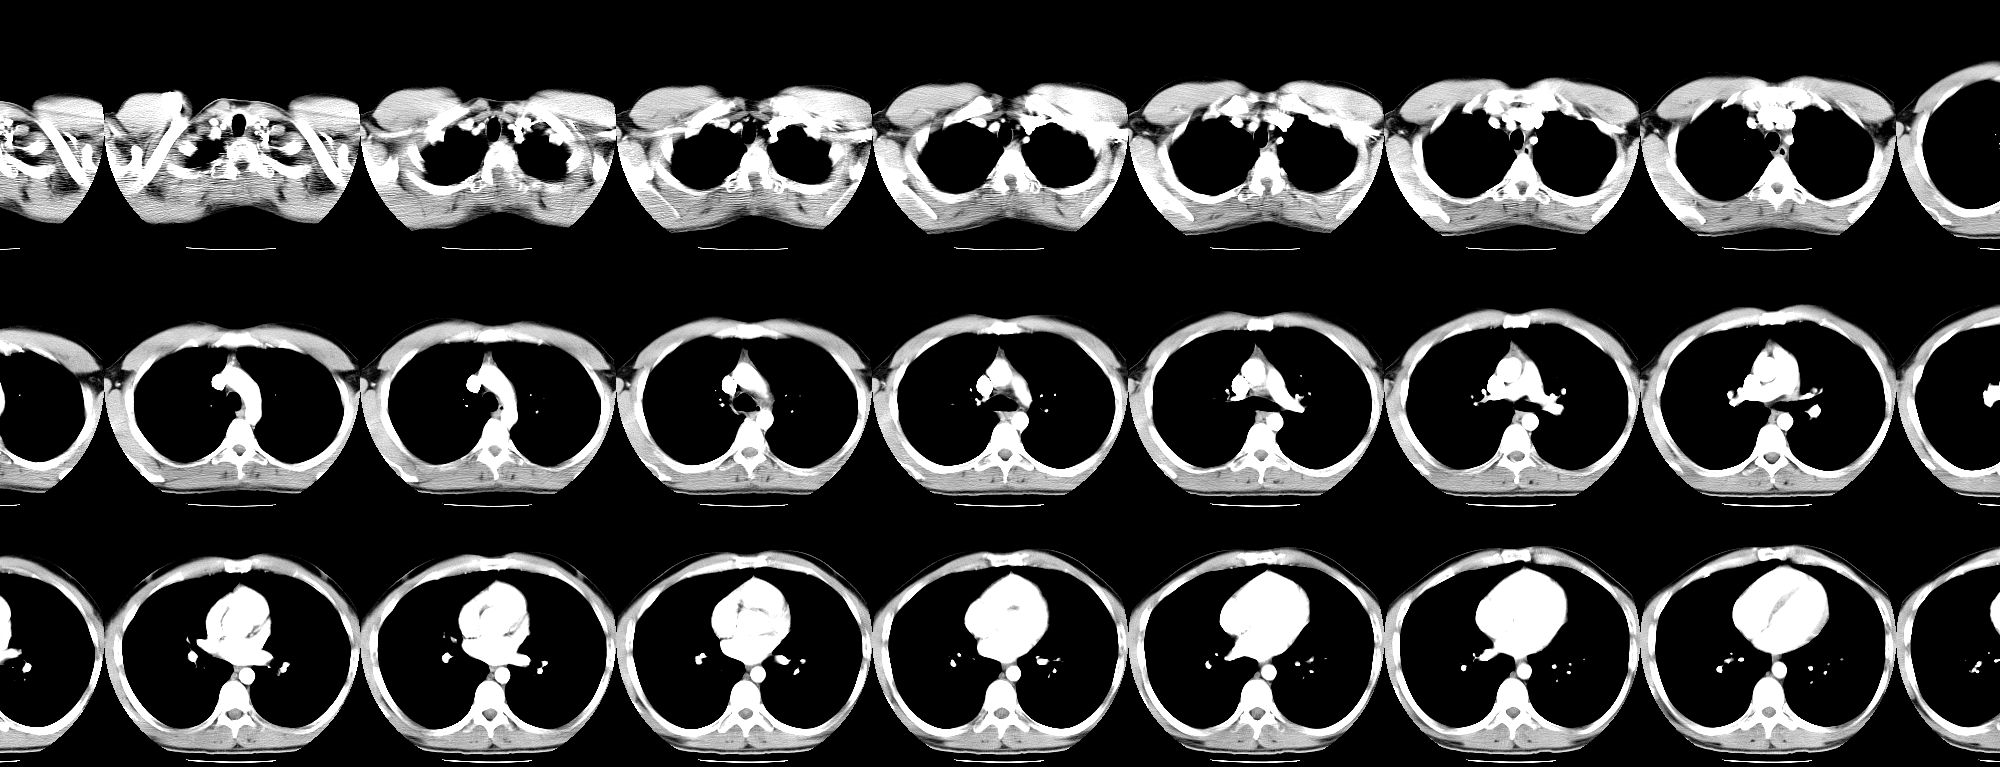

Este proyecto tiene como objetivo plástico el arrojar una nueva perspectiva sobre los sonidos y ruidos que se producen en una prueba de resonancia magnética, intentando con ello ampliar los horizontes de comprensión que tenemos sobre ella.

Un segundo objetivo es el dar a conocer diversos aspectos de esta prueba que normalmente son poco ejemplificados, sus intensos ruidos. Estímulos que sin embargo son uno de los mayores factores que angustian durante la prueba. Al darlos a conocer y además brindar una perspectiva plástica de ese entorno, el paciente puede prepararse mejor para la situación que va a experimentar e incluso atender al proceso que está viviendo de una forma más creativa y positiva. En este sentido el proyecto RE(((SON)))ANCE puede tener valores terapéuticos.